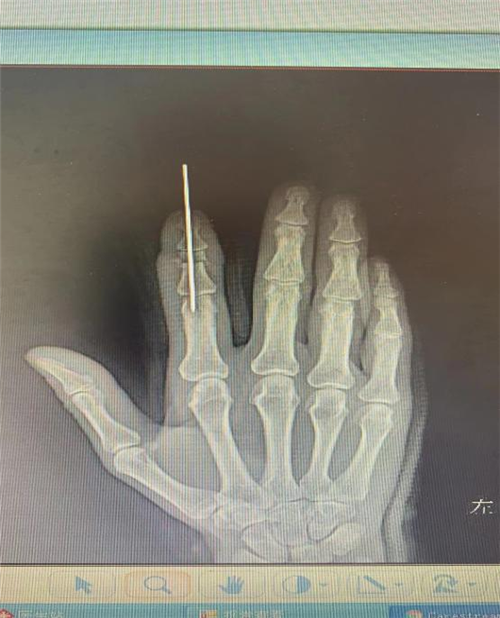

李明医师在安抚患者情绪的同时,立刻组织术前讨论,为患者制定详细的手术方案,对血管口径、动、静脉比例,以及骨折内固定等手术细节迅速做出预案,以最快的速度将患者送入手术室。

无影灯下的清创,骨折的内固定,显微镜下的动静脉血管的探查及吻合,手术有序高效的进行着,经过约6个小时的不懈努力,患者断指顺利再植,手术完成即刻,离断的食指立即变得红润,指腹毛细血管迅速充盈,干瘪的指体恢复饱满。